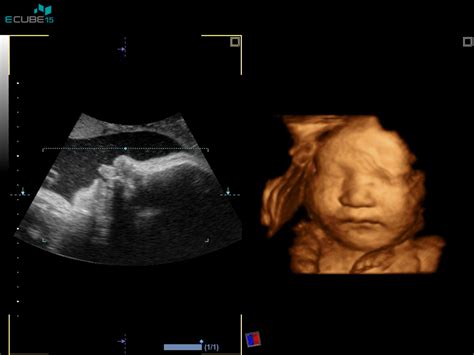

Diagnoza in Klinična Slika

Diagnoza cističnega higroma se običajno začne s temeljito klinično oceno, ki vključuje ultrazvočni pregled. Na ultrazvoku lahko zdravniki opazijo prisotnost cistične tvorbe. V primeru suma na cistični higrom se lahko izvajajo dodatne genetske preiskave, kot je biopsija horionskih resic ali amniocenteza, da se oceni morebitna povezanost z genetskimi nepravilnostmi. Simptomi cističnega higroma se lahko razlikujejo glede na njegovo velikost in lokacijo. Večji higromi lahko povzročajo pritisk na sosednje strukture, kar lahko vodi do težav pri hranjenju, dihanju ali premikanju.